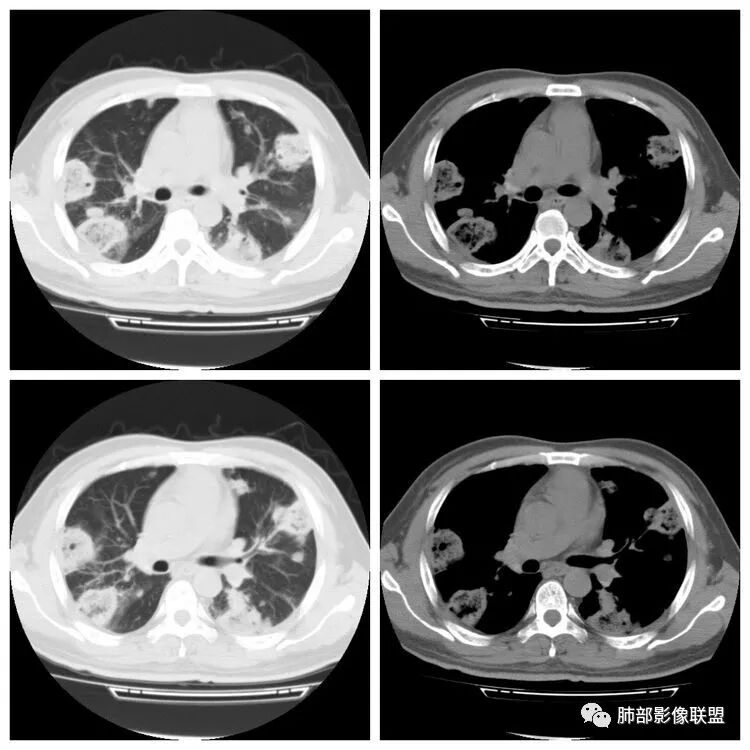

下面是一例几乎一样的肺克:

南边:反晕征是毛霉菌的特点按理单从影像:毛霉菌更多符合因为细菌性的特点:液气平面,囊,这个没出现

肺克的影像表现(唐绍宏总结):分布:单侧上叶病变,以右肺上叶多见;患者长期卧床则双脚下肺后基底段分布(国外下肺多见,可能与平均寿命长,卧床及住托老机构多有关) ;如多叶段病变,则以肺上叶后段或下叶后基底段为最明显形态:气管壁增厚、磨玻璃、小叶实变、节段实变、大叶实变,坏死小空洞(直径小于2cm) ,少量胸腔积液50%、脓胸20%特点:早期气管壁增厚较明显、广泛,越靠近病灶越明显,越靠近肺门越明显,见于实变病灶外,偶尔见于磨玻璃影内(支气管通气征) ;未经抗生素治疗,实变病灶内无支气管通气征;早期即可出现坏死,无论坏死还是空洞,绝大多数直径小于2cm (可能与此菌有厚夹膜有关,参考隐球菌)